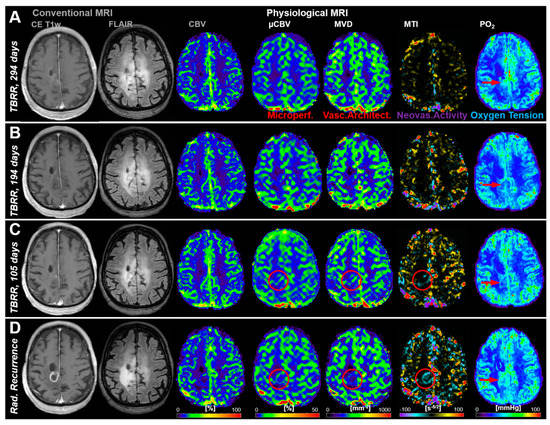

3.2. Follow-Up Examinations with Conventional and Physiological MRI

3.3. Time Courses of MRI Biomarker Changes Preceding Radiological AG Recurrence